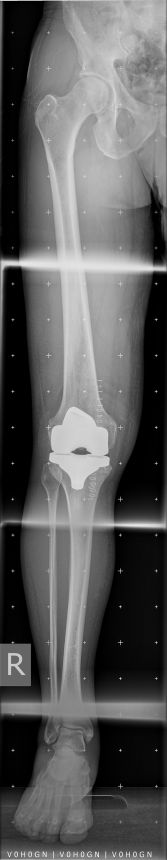

Was macht mein Knie heute? Es ist schon komisch, welche Antworten ich auf meine oft gestellte Frage bekam, wie lange es dauern wird, bis ich wieder beschwerdefrei laufen (sic!) kann. Zunächst war die Rede von drei, dann vier Monaten. Dann wurden es schon sechs Monate – bis zu einem Jahr. Von einem Bekannten hörte ich nun, dass er fast zweieinhalb Jahre brauchte, bis er wieder so gehen (sic!) konnte, wie er es sich wünschte. Heute nach fast neun Monaten seit der OP habe ich immer noch Beschwerden, leichte Schmerzen zwar nur, besonders in der Nacht beim Schlafen, beim Treppenhinabgehen oder beim Anziehen (Socken, Hose), aber immer noch zieht und ziept es. Im Grunde sollen durch ein neues Kniegelenk lediglich die Aktivitäten des täglichen Lebens wieder schmerzfrei ermöglicht werden. Wer mehr möchte, der muss selbst zusehen, wie er klarkommt. Ein menschliches Kniegelenk beinhaltet sehr komplexe Bewegungsabläufe, die durch eine Gelenkprothese nicht vollständig nachgebildet werden können. Bei einer Hüftprothese ist die ärztliche Kunst schon einen Schritt weiter. Schön, wenn man solches, wenn auch verspätet, doch noch erfährt.